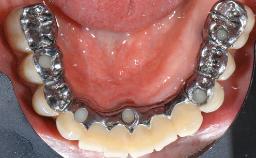

This case describes the ongoing management of a 64-year-old healthy, non-smoking female patient with erosive oral lichen planus (OLP) affecting the gingivae and the buccal and lingual mucosa. The peri-implant mucosa was also affected subsequent to implant placement. The patient had osseointegrated implants (four in the maxilla, four in the mandible) placed following extraction of hopeless teeth and a healing period. The patient had a history of OLP prior to implant placement and had been referred to an oral-medicine specialist for definitive diagnosis and treatment. She exhibited generalized oral mucosal involvement. Following a clinical assessment, biopsy, and blood tests, she was treated with topical corticosteroids. Systemic prednisolone was reserved for severe flare-ups. Amphotericin lozenges were used in combination with corticosteroid treatment to prevent the development of oral candidiasis.

# of Implants 8

Type of Implants Two-Piece

Retention Screw-retained, with 4 or more splinted implants Screw-retained, with 4 or more splinted implants